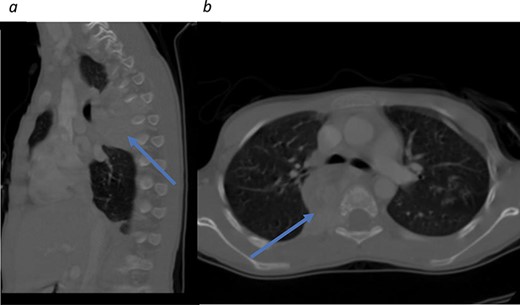

Initial CT scans. (a) Sagittal view, tumor noted in the mediastinal area between T4–T7. (b) Axial view showing tumor causing no narrowing of the spinal canal.

A 6-year-old female with history of on and off cough associated with chest pain was seen in another hospital and diagnosed with mediastinal mass discovered on chest X-ray. She was referred to our hospital for further investigation and management. The patient denied history of palpitation, flushing, headache or any neurological symptoms. On clinical examination, she was a stable patient with no sensory or motor deficit. Routine laboratory work was carried out and results were unremarkable. Contrast-enhanced computerized tomography (CT) scan was done to further investigate the mass and showed a highly vascular right posterior mediastinal tumor measuring 3.29 × 1.2 × 4.6 cm extending from the level of T4 down to T7 encroaching the carina and right main bronchus and sparing the vertebrae (Fig. 1). The treating team (Thoracic Surgery) and the family decided to proceed with surgery and the patient was taken for video-assisted thoracoscopic surgery (VATS) for tumor excision through lateral approach. Intraoperatively, the tumor bled profusely, and the procedure was converted to open thoracotomy to control the bleeding. The tumor was resected completely, and a specimen was sent for histopathology. Pathology report returned back to show benign paraganglioma (Fig. 2). The need for further investigations was explained, as the disease could be associated with other benign tumors that should be identified.